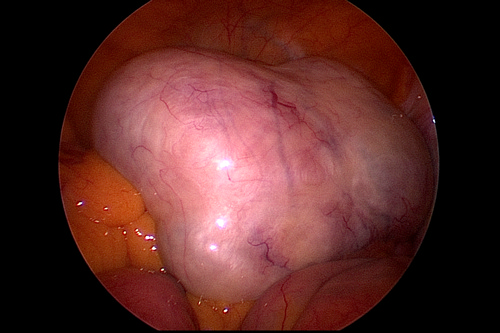

「陳小姐的卵巢瘤屬於良性畸胎瘤」李佩蓁醫師表示,一般卵巢畸胎瘤都是沒有症狀,不會痛也沒有感覺,一旦腫瘤長到超過五公分,因重量不均勻就有較高的機率因為運動或姿勢改變而扭轉,導致月經異常或卵巢缺血引起下腹痛或劇烈腹痛,這時就需以手術來切除腫瘤。

圖:腹腔鏡下右側卵巢瘤。